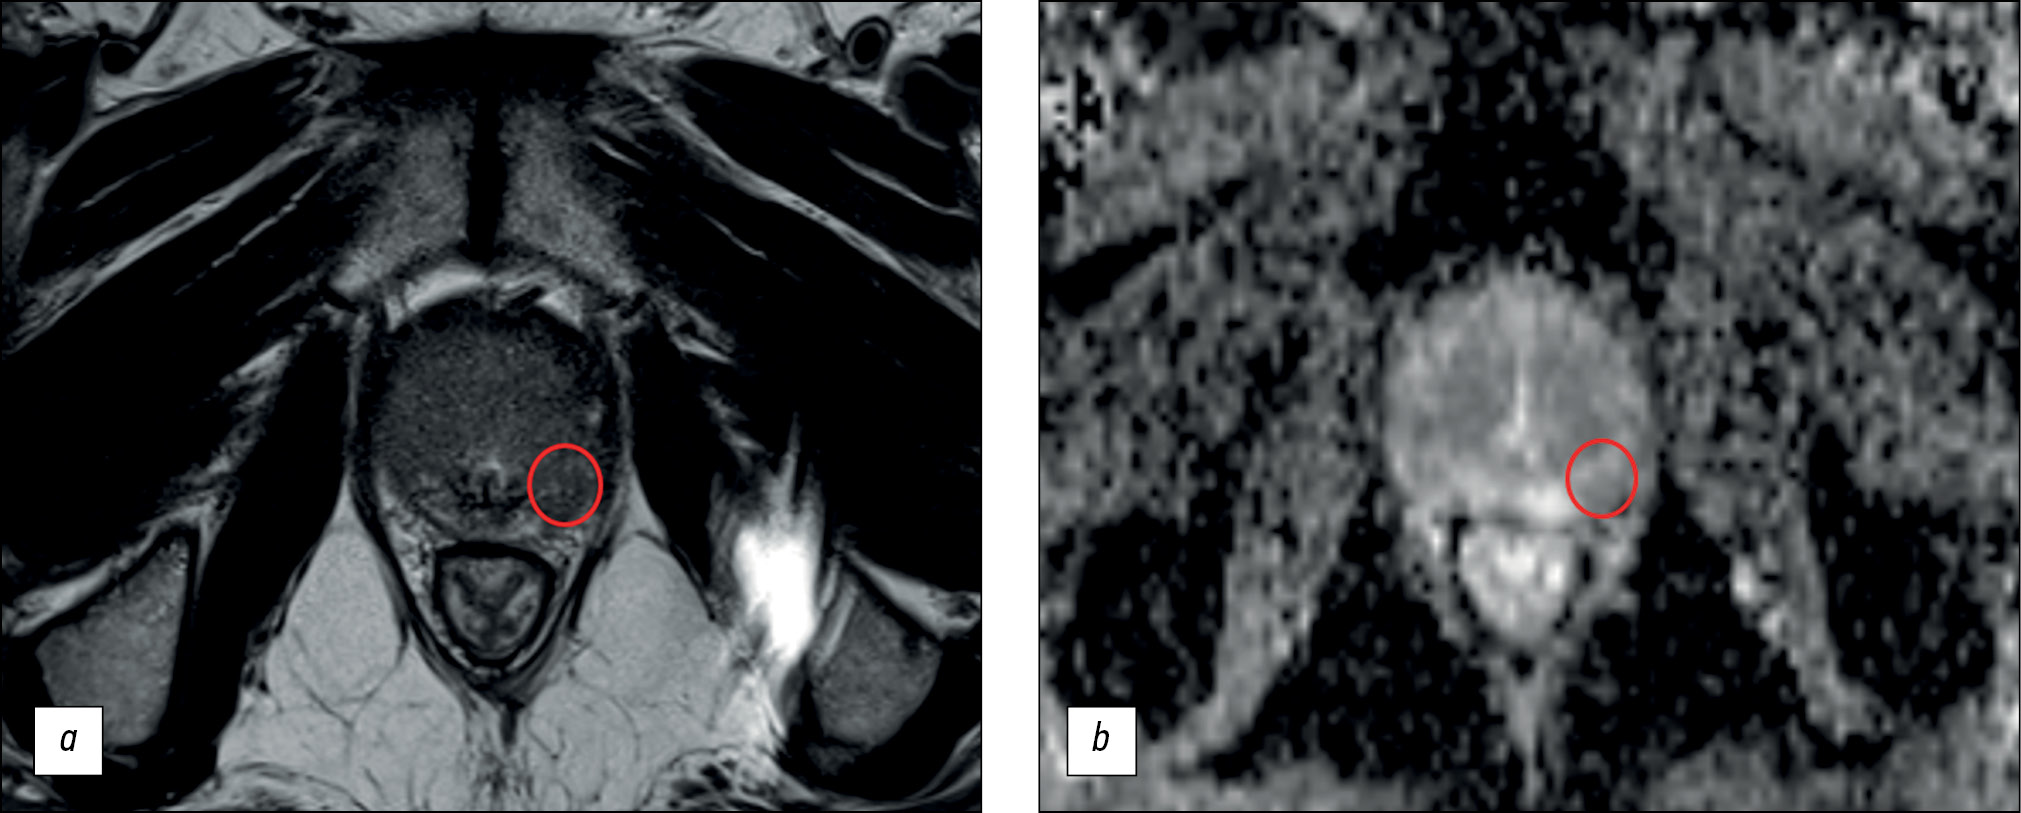

BACKGROUND: Magnetic resonance imaging can detect clinically significant prostate cancer and diagnose extracapsular extension and cancer stage. A scanning protocol that includes only T2-weighted and diffusion-weighted images represents a viable alternative to multiparametric magnetic resonance imaging provided that the high diagnostic accuracy of the test is maintained. In recent studies, biparametric and multiparametric magnetic resonance imaging demonstrated slight differences in the diagnostic accuracy in detecting prostate cancer.

AIM: To compare the diagnostic accuracy of biparametric and multiparametric magnetic resonance imaging for the detection of clinically significant prostate cancer using PI-RADS v2.1 with magnetic resonance imaging-guided multifocal biopsy as the gold standard.

MATERIALS AND METHODS: This retrospective study initially processed the medical records of 126 patients. The inclusion criteria were as follows: presence of PI-RADS 2.1 multiparametric magnetic resonance imaging, clinical information on free and bound prostate-specific antigen blood levels, a multifocal prostate biopsy performed, and a time interval between magnetic resonance imaging and biopsy of no more than 14 days. Three investigators (radiologists with <2, 2–5, and >5 years of experience) independently evaluated biparametric magnetic resonance imaging of the prostate for the presence of pathological foci. After 2 weeks, the researchers evaluated the multiparametric magnetic resonance imaging dataset of the prostate. Each lesion detected, starting from PI-RADS category 3, was compared with the result of a multifocal fusion biopsy. The biopsy result was presented as a sum of Gleason scores, and a Gleason score of ≥7 was considered clinically relevant. According to magnetic resonance imaging data, findings meeting PI-RADS criteria 4 and 5 were considered tumor foci.

RESULTS: The best values of sensitivity and specificity of foci detection on magnetic resonance imaging of the prostate gland were 62.5% and 74.6%, respectively. The highest diagnostic accuracy achieved was 70.1%. Magnetic resonance imaging had higher specificity rates for detecting prostatic foci when interpreted by radiologists with 2 years and >5 years of experience.

CONCLUSION: Both biparametric and multiparametric magnetic resonance imaging of the prostate demonstrated suboptimal diagnostic accuracy. The sensitivity and specificity of the method tended to improve with increasing experience of the radiologist. Biparametric protocols of prostate scanning have a definite economic advantage over multiparametric protocols because of the absence of contrast agents and consumables and a significant decrease in magnetic resonance scanner loading time; however, their use can lead to a decrease in the diagnostic accuracy of the method.